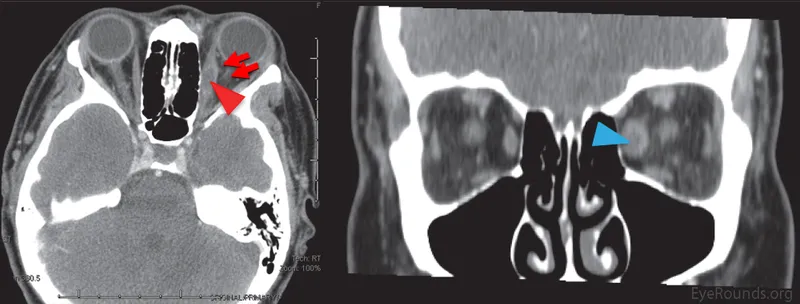

- Orbital Cellulitis: POSTERIOR. EMERGENCY! Proptosis, painful ophthalmoplegia, ↓ vision, afferent pupillary defect (APD).

Sources: Sinusitis (esp. ethmoid), dacryocystitis, trauma, dental.

⭐ > In children, ethmoid sinusitis is the most common precursor to orbital cellulitis.